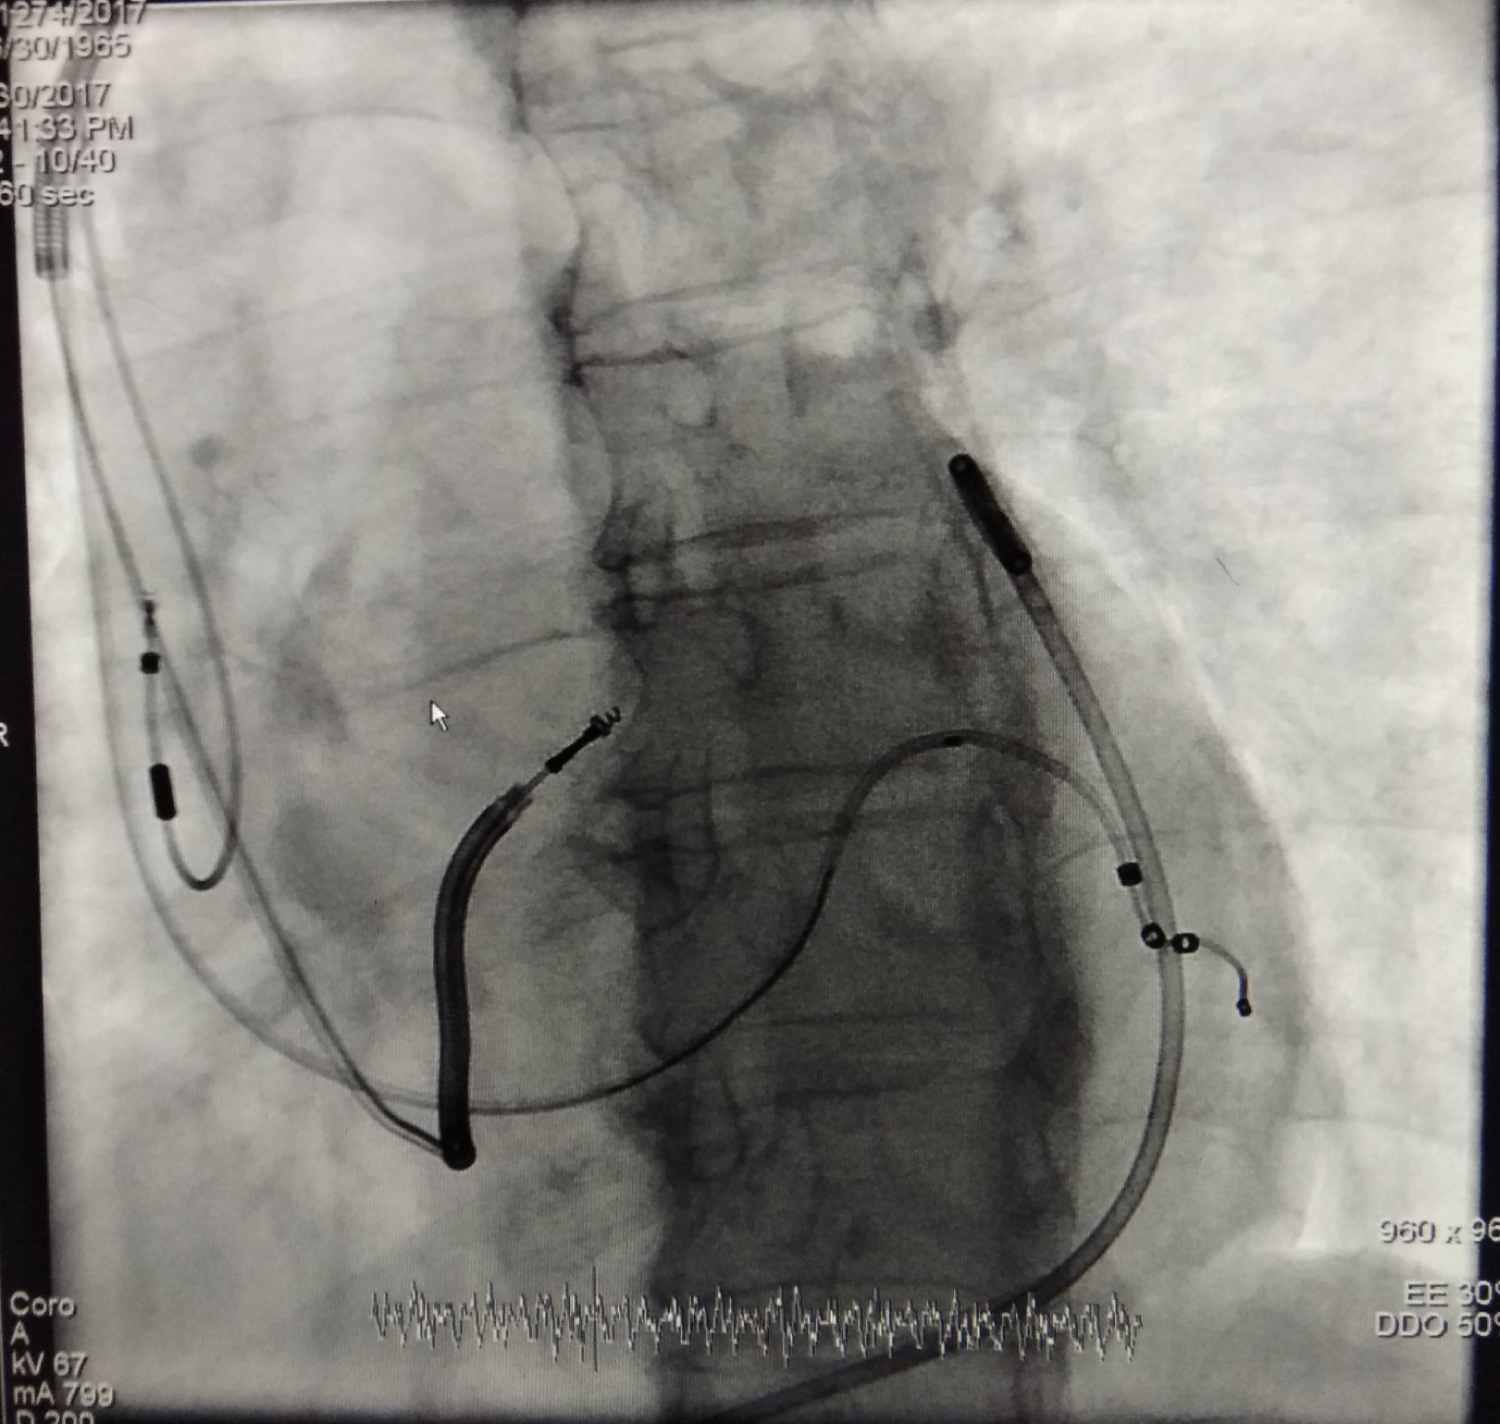

CRT-D implantation has become a standardised treatment for patients suffering from Heart Failure with reduced Ejection Fraction (HFrEF). Patients with left ventricular ejection fraction (LVEF) below 35% along with Left Bundle Branch Block (LBBB) pattern with wide QRS duration are the most benefitted one post placement. Implantation of CRT-D needs expertise so that proper left ventricular lead placement can be done. It also depends on anatomical suitability of Coronary Sinus (CS). Most of the time operators are concerned about the LV lead placement. However sometimes RV lead which contains ICD coil sometimes poses difficulties to position on the RV apical segment. Improper threshold, loss of trabeculation, dilated RV cavity all are causes for failure to place RV lead in proper position. Septal placement of RV lead is an alternative site in such scenario. It is quite difficult to place such heavy lead in septum. Here I have reported a case where CRT D pacemaker implantation has been done with placement of RV lead in Septal position in a patient of HFrEF with pericardial effusion. Pericardiocentesis was done with placement of pigtail catheter and she was planned for CRT - D placement. Placement of RA and LV lead was done smoothly in this case with a good threshold and impedance. However, ICD lead in RV apical position could not be done due to smooth RV cavity. Therefore, it was placed in septum and procedure was successful. Figure 1 image, showing all 3 leads in LAO 27-degree position along with pigtail catheter in pericardial space. Video 1 showing synchronised contraction in the LAO 27-degree view. Post implantation QRS was significantly narrow and she was kept on biventricular pacing along with proper medications.

Figure 1: Showing eeptal CRT-D (RA lead, eeptal ICD lead and LV lead) in LAO view.